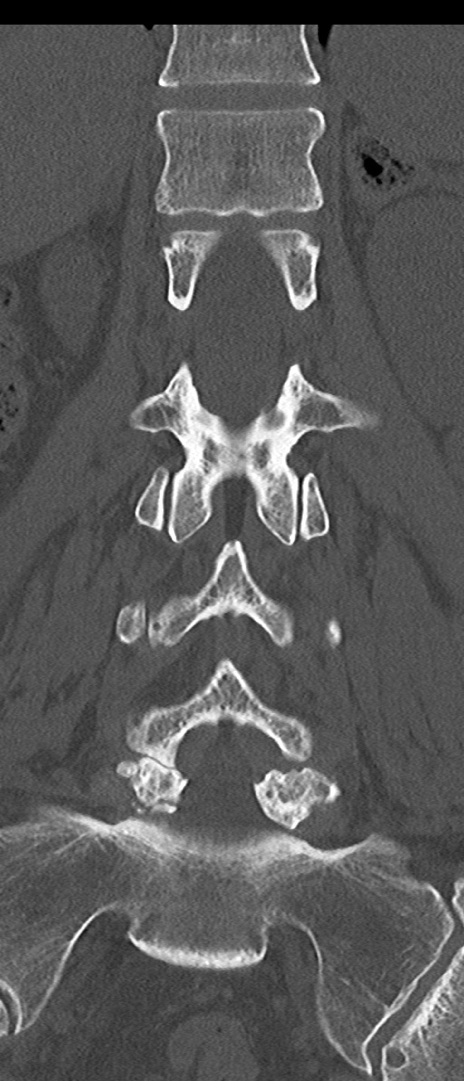

腰椎CT

横断像